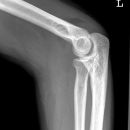

Ellenbogenluxation